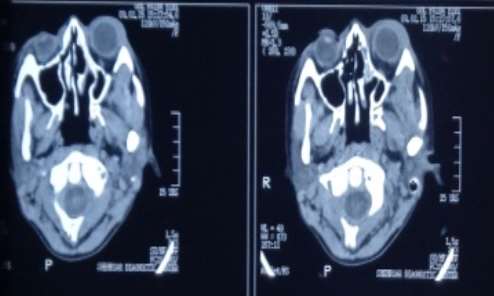

CT scan orbit (Coronal View): Bilateral Superior Orbital Masses

Lab investigations: Hb 11.1 g/dl, RBC 4.27 million/cmm, Hct 32.4 %, MCV 76 fl, MCH 25.9 pg, MCHC 34.2 g/dl, Platelet count 328000/cmm, TLC 11000/cmm, normocytic normochromic picture with DLC showing 80% neutrophils, 15% lymphocytes and 5% monocytes on peripheral smear, ESR 70 mm/1st hour, negative HbS and HCV screening, negative PPD and sputum AFB, normal Liver function tests and normal Renal function tests. Chest X-ray was normal, U/S and CT scan of the abdomen and pelvis were normal. CT scans of the orbits showed bilateral superior orbital masses and mild proptosis of the left eye.